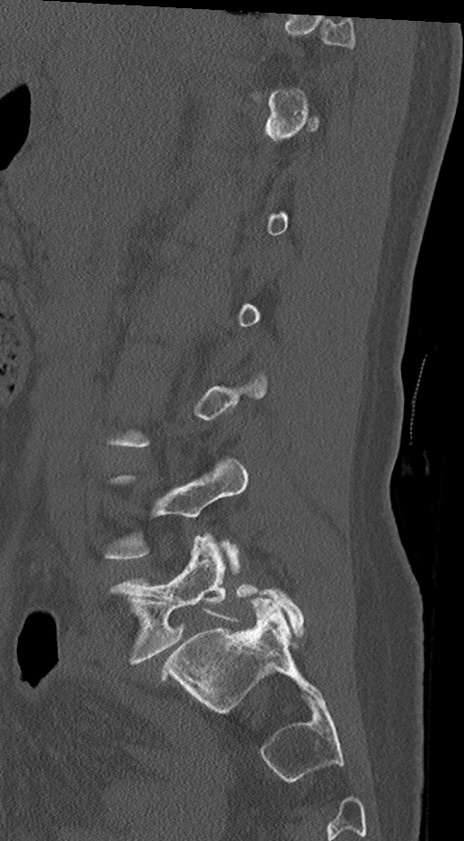

腰椎CT

冠状断像